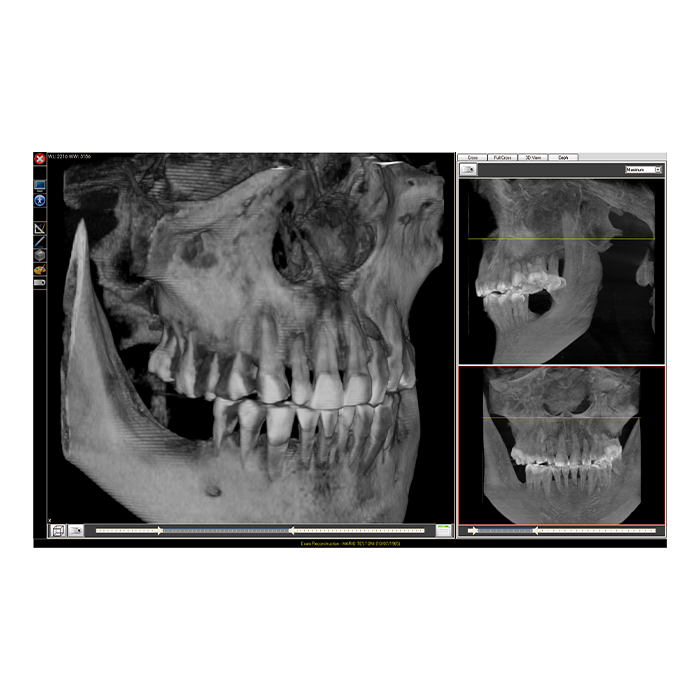

Система Fona XPan 3D представляет собой современное решение для панорамной и 3D-визуализации в стоматологической практике. Это оборудование нового поколения, которое объединяет в себе проверенную надежность панорамной съемки и передовые возможности трехмерной томографии. Система создана для того, чтобы предоставить врачу-стоматологу, ортодонту или челюстно-лицевому хирургу максимально полную диагностическую информацию для постановки точного диагноза и планирования эффективного лечения.

Fona XPan 3D — это инвестиция в качество диагностики и безопасность пациентов. Система позволяет за одно сканирование получить как обзорный панорамный снимок, так и прицельные 3D-томограммы интересующей области, минимизируя лучевую нагрузку и экономя время врача и пациента.

- Многофункциональность в одном аппарате: Одно устройство заменяет несколько. Вы получаете возможность выполнять панорамные снимки (ортопантомограммы), 3D-томографию (КЛКТ) отдельных сегментов, телерентгенографию (ТРГ) в боковой проекции, а также снимки височно-нижнечелюстных суставов (ВНЧС).

- Высокая точность и детализация: Цифровой датчик с высоким разрешением обеспечивает получение четких изображений, на которых видны мельчайшие детали: состояние корневых каналов, начальные кариозные поражения, структура костной ткани для имплантации.

- Мощное программное обеспечение: В комплекте поставляется профессиональное ПО для обработки, анализа и хранения снимков. Оно позволяет проводить измерения, строить 3D-модели, планировать установку имплантатов и легко интегрируется с другими цифровыми системами клиники.

3D-снимок (КЛКТ) предоставляет объемное изображение, позволяя врачу увидеть область интереса в трех плоскостях и оценить плотность тканей. Это исключает наложение структур, что критически важно для планирования имплантации, поиска дополнительных каналов или диагностики сложных переломов.